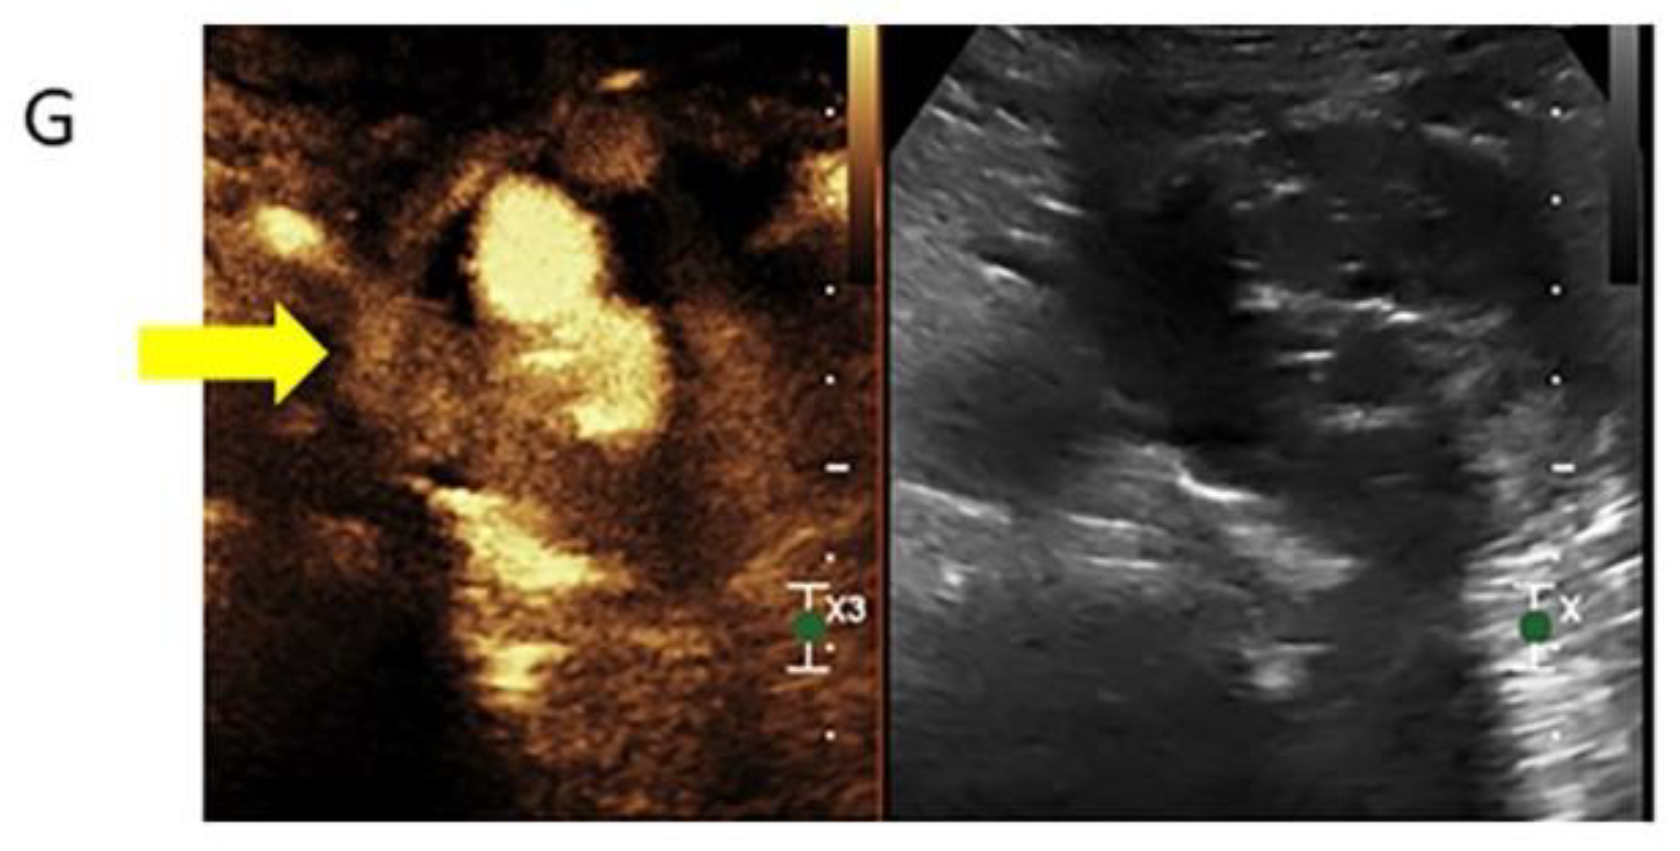

3.2.3. Contrast-Enhanced Ultrasound